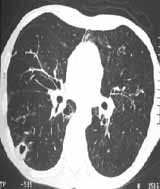

Uno de los pacientes cuya radiografía mostró opacidades nodulares mal definidas tenía una TAC con nódulos cavitados múltiples subpleurales (Figura 4).

[enc_su_column size=”1/2″]

Figura 4. Radiografía y TAC que muestran múltiples nódulos cavitados de localización subprleural.[/enc_su_column]